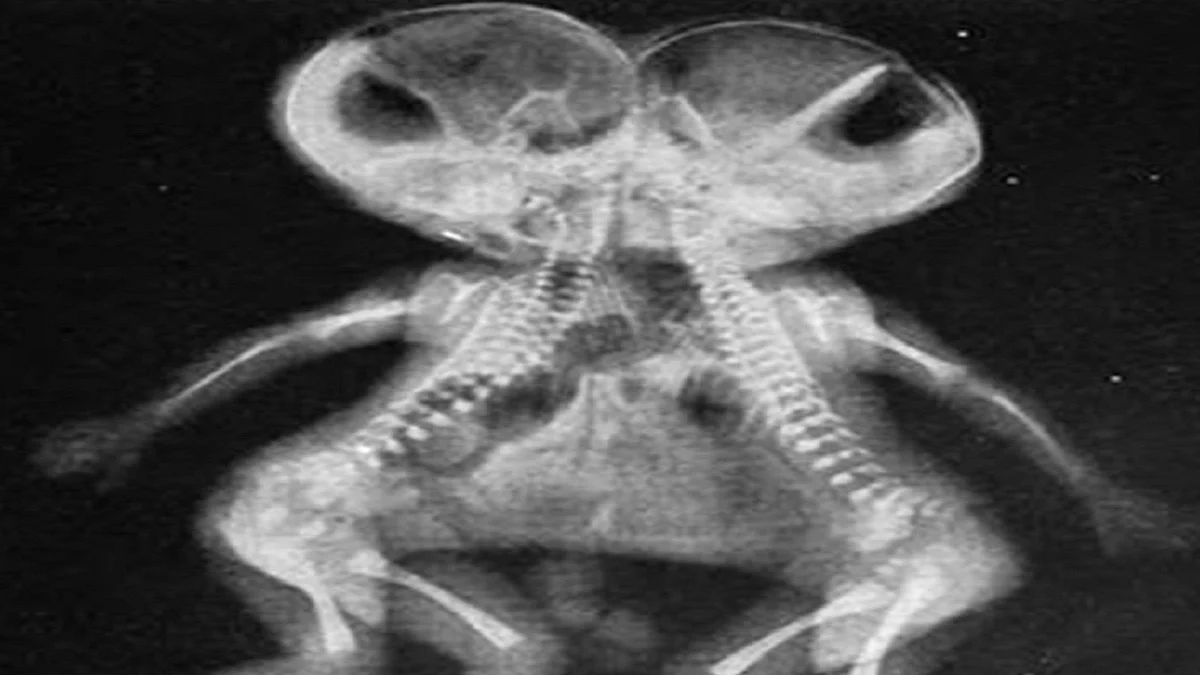

The twins are omphalopagus -- they are joined at their bellies. The survival rate in such cases is only 5 to 25 per cent, according to medical experts. Such twins generally share a liver but sometimes also the lower part of the small intestine and colon.

Usually conjoined babies require surgical delivery by caesarean section due to their anatomy but in this case they were born through a normal delivery at home.